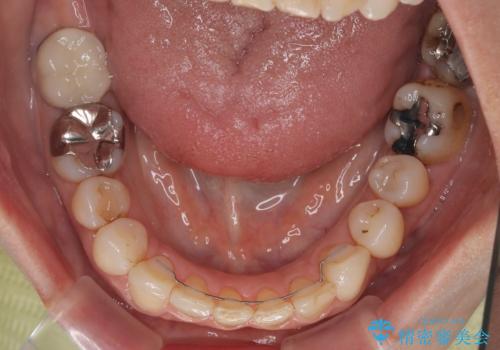

- 上下前歯のデコボコと、治療途中の歯を気にして来院された患者様です。

ご家族がインビザラインにて矯正治療を行っていたため、ご本人の希望によりインビザラインによるマウスピース矯正を行うこととしました。

根管治療が必要な歯は事前に処置を行った上で矯正治療を開始し、概ね歯列が整ったところでセラミッククラウンなどに置き換え、その後インビザラインを1セット使用して仕上げていくこととしました。